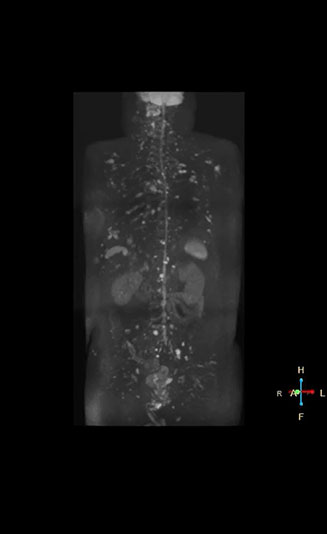

Radiologist Hiroshi Nobusawa, MD, PhD, explains that the coronal DWIBS protocol for whole body DWI is excellent for visualizing lesions in oncology patients. “About 90% of the DWIBS exams are done in this type of patients. The remainder of DWIBS exams are performed to gain information in cases of fevers of unknown origin,” he says. in image acquisition and postprocessing algorithms.”“mDIXON TSE sequences allow simultaneous characterization of morphological changes from the in-phase T2-weighted images and visualization of edematous changes, thanks to the water T2-weighted images from the same acquisition. Anatomical and morphological considerations could be a partial or complete ligament tear, a bony avulsion or hematoma.” “For soft tissue assessment mDIXON brings similar benefits. For example in one T2-weighted mDIXON TSE acquisition, having the multiple contrasts helps us assess abnormalities in peripheral nerves fascicles, which may be due to anatomical or inflammatory changes..” “In peripheral joints, we get good image quality in difficult areas with mDIXON TSE. Fat suppressed images appear homogeneous over the entire image, even with large coverage at 3.0T – for instance in scapular or hip girdles – or in the bearing areas or around metal prostheses*, where fat suppression is often deficient with STIR or spectral fat suppression, causing diagnostic difficulties. If a diagnostic image is right the first time, we don’t need to repeat or add a sequence.” “mDIXON TSE sequences allow simultaneous characterization of morphological changes from the in-phase T2-weighted images and visualization of edematous changes, thanks to the water T2-weighted images from the same acquisition. Anatomical and morphological considerations could be a partial or complete ligament tear, a bony avulsion or hematoma.” “For soft tissue assessment mDIXON brings similar benefits. For example in one T2-weighted mDIXON TSE acquisition, having the multiple contrasts helps us assess abnormalities in peripheral nerves fascicles, which may be due to anatomical or inflammatory changes..”

“In-phase and out-phase sagittal T1-weighted FFE images help us to visualize and further characterize bone lesions such as metastasis and bone-marrow hyperplasia that have high signal on DWI. These images are also used throughout radiotherapy, to monitor changes in the fatty bone marrow.”